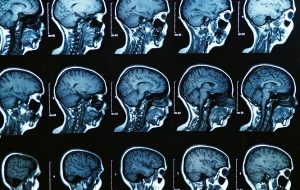

İlk Kez İnsan Beyninin Doğumdan Ölüme Kadar Nasıl Değiştiği İzlendi

İlk Kez İnsan Beyninin Doğumdan Ölüme Kadar Nasıl Değiştiği İzlendi Dünyanın dört bir yanındaki yüzlerce bilim insanı, dünyanın ilk beyin